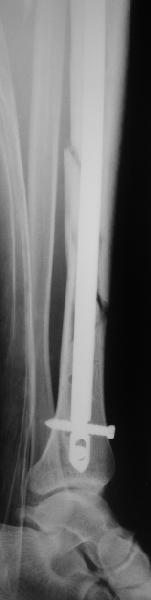

"Ходит с ограниченной нагрузкой на ногу. Направлен из травмпункта по поводу оставшегося смещения отломков. У нас разделилось мнение коллег по вопросу - есть ли необходимость в закрытом интрамедуллярном реостеосинтезе с исправлением оси или только ограничиться динамизацией гвоздя"

Техника введения штифта в дистальные переломы голени отличается от введения в c/3 диафиз. В дистальном отделе штифт надо ввести поглубже и блокировку внизу сделать на все возможные дистальные отверстия. В верхней части короткий штифт создает запас для будущей динамизации.

Одним из идеальных штифтом для лечения дистальных переломов голени является от Synthes Expert Nail, где имеется 4 возможные отверстия для дистальной блокировки, которые в различных направлениях создают дополнительную стабильность.

На снимке сохранен небольшой вальгус, но имеется нормальная аппозиция медиального кортикального слоя и поэтому трудно согласится что здесь имеется неправильно фиксированный перелом. Для идеального сопоставления таких косых переломов надо открывать фокус травмы, но тогда меняется философия фиксации.

Навряд ли рискованные манипуляции в фокусе травмы или ре-остеосинтез улучшит результат кроме рентгенологической картины.

Для предупреждения осложнении можно оставить как есть, потому что всего месяц с момента операции и не видно признаков несостоятельности остеосинтеза.

Отсутствие болей показания к нагрузке и после восстановления движения в суставе через пару-три недели можно сделать динамизацию. За редким исключением, обычно такие “неправильно фиксированные” переломы сростаются в срок.